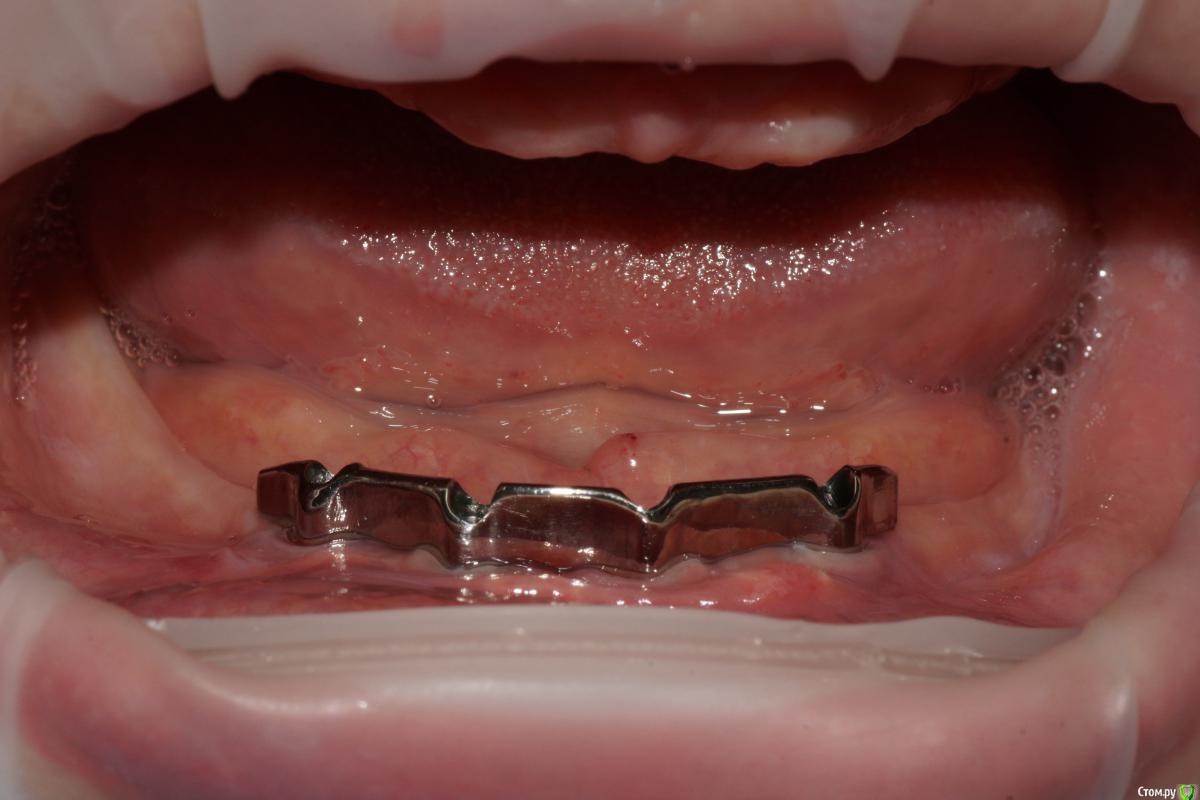

Evikrol Опубликовано 25 ноября, 2016 Поделиться Опубликовано 25 ноября, 2016 В области каких зубов выходят шахты дистальных имплантатов? Ссылка на комментарий

togrul Опубликовано 25 ноября, 2016 Автор Поделиться Опубликовано 25 ноября, 2016 В области каких зубов выходят шахты дистальных имплантато В области каких зубов выходят шахты дистальных имплантатов?Добрый день. в области клыков . снимок на работе Ссылка на комментарий

Aquarius Опубликовано 25 ноября, 2016 Поделиться Опубликовано 25 ноября, 2016 (изменено) Кучно стоят Я стараюсь разнести по саггитали http://s018.radikal.ru/i504/1611/d2/edee533725fa.jpg Изменено 25 ноября, 2016 пользователем Aquarius 4 Ссылка на комментарий

togrul Опубликовано 26 ноября, 2016 Автор Поделиться Опубликовано 26 ноября, 2016 Кучно стоят Я стараюсь разнести по саггитали В данном случае не было условий. Пациентка до этого носила сьемники 15 лет. Ссылка на комментарий

Evikrol Опубликовано 26 ноября, 2016 Поделиться Опубликовано 26 ноября, 2016 что значит условно съемный? Протез или съемный или несьемныйУсловно-съемный, протез который может снять только доктор, на винтовой фиксации. Когда будет готов кейс, обязательно выложу. В данном случае не было условий. Пациентка до этого носила сьемники 15 лет.http://s017.radikal.ru/i413/1611/f8/e80b545e1b3d.jpgТут тоже был съёмник лет 20 Ссылка на комментарий

max9108 Опубликовано 29 ноября, 2016 Поделиться Опубликовано 29 ноября, 2016 Но ведь тут пациентка сама снимает нижний протез с балки? Ссылка на комментарий

togrul Опубликовано 29 ноября, 2016 Автор Поделиться Опубликовано 29 ноября, 2016 Но ведь тут пациентка сама снимает нижний протез с балки?Все верно. Ссылка на комментарий